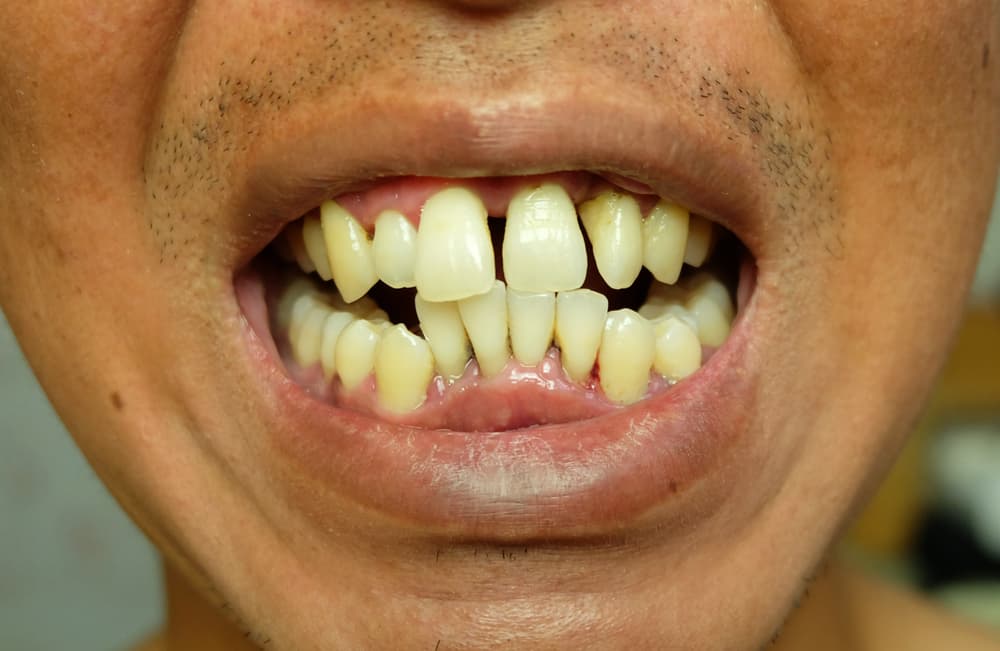

Digital Smile Design

Transform patient consultations with AI-powered smile simulations. Show before/after results in minutes, not weeks.

Smile design spotlight

Show patients their future smile in minutes.

Turn uncertainty into confidence with visual before-and-after simulations that make treatment decisions easier.

Show outcomes before treatment starts

Turn consults into visual conversations patients can understand in the first visit.

Shorten decision cycles

Help patients commit faster with side-by-side treatment previews and clearer expectations.

Improve high-value case acceptance

Connect clinical recommendations to visible cosmetic and functional outcomes.